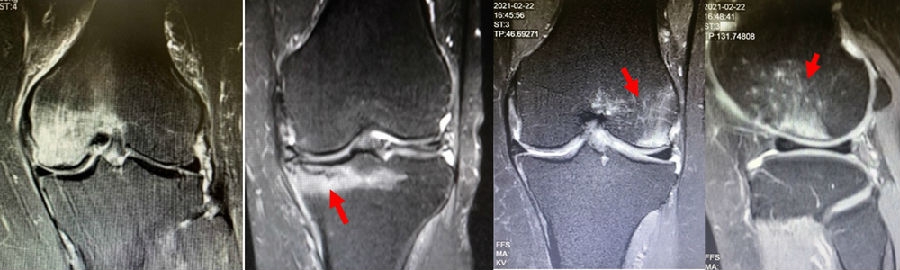

SONK与内侧半月板后根部损伤,有国外学者在SONK患者中通过MRI及关节镜检查,常可发现合并内侧半月板后根部的撕裂,该发生率可达到80%(24/30), 15例完全撕裂,9例部分撕裂。结果表明SONK可能与内侧半月板后根部撕裂后,导致股骨负重区的应力集中、软骨下骨髓水肿有关。

膝内翻 内侧半月板根部撕裂

应力源性理论